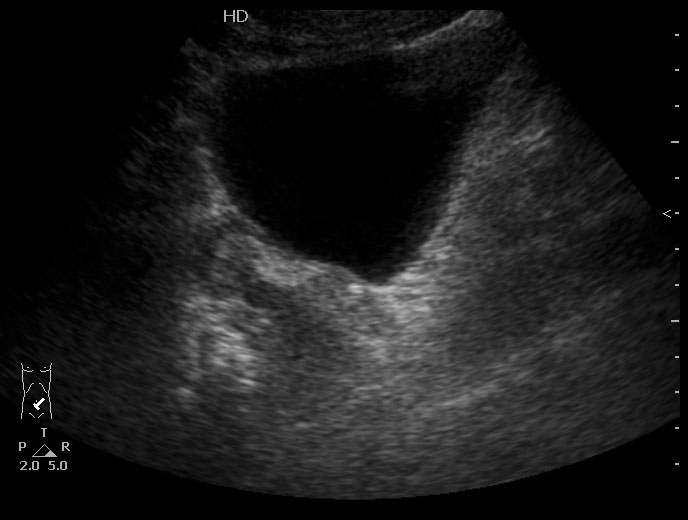

Особенность этого случая заключается в том,что достаточно выраженные боли не сопровождались расширением ЧЛС, поэтому формула "отсутствие расширения ЧЛС на высоте болей практически исключает уретеролитиаз" здесь оказалась нерабочей.

Но это первый случай лет за 20.

Проводить инспекцию мочеточника пришлось из-за изменений почки - выпота и повышения эхогенности патенхимы. Как вариант рассматривался тромбоз ПА, но доплерографически он был исключен.

В общем-то, редкий случай.